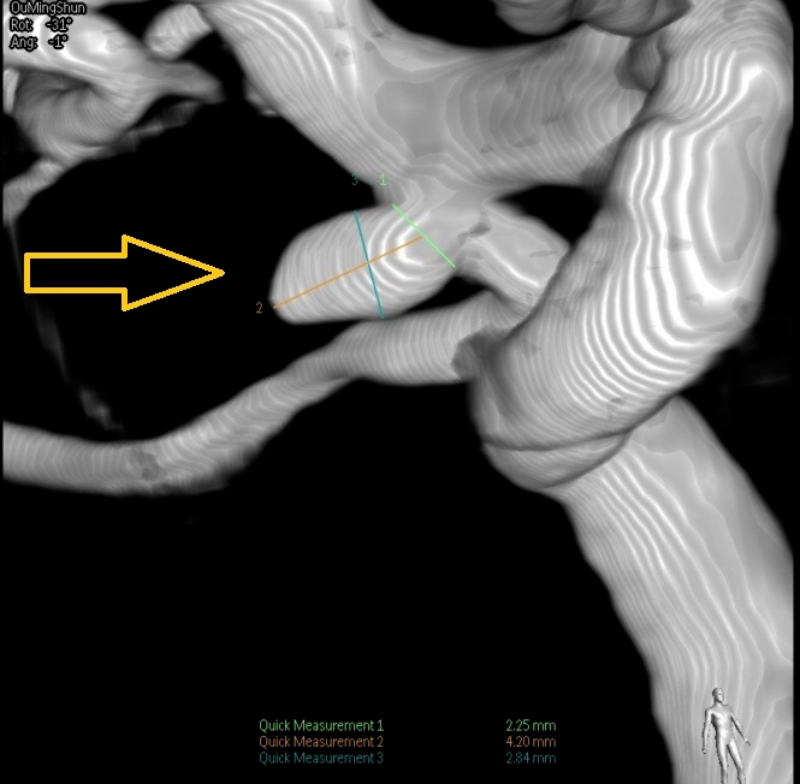

將患者收入神經(jīng)外科病房后,值班醫(yī)生詳細(xì)詢問了兩位病人的發(fā)病情況,仔細(xì)地做了體格檢查并閱讀了患者的頭部CTA,考慮他們的動脈瘤已經(jīng)破裂,如果再次破裂,后果極其嚴(yán)重,死亡率接近50%!為此,患者入院后,急診醫(yī)學(xué)科緊急聯(lián)系導(dǎo)管室,開啟 急診腦卒中綠色通道,在完善了腦血管造影術(shù)后(Digital subtraction angiography,DSA),兩位患者顱內(nèi)的動脈瘤及全部腦血管情況均已清楚地顯示了出來。

黃小山詳細(xì)地與患者家屬解釋了疾病情況及手術(shù)方案、風(fēng)險,患者家屬表示理解,并對醫(yī)院的技術(shù)能力及設(shè)備非常信任,愿意在博羅分院進(jìn)行手術(shù)治療。緊急完善術(shù)前準(zhǔn)備后,在神經(jīng)外科主任醫(yī)師羅洪海的指導(dǎo)下,主任醫(yī)師晏廣及主任醫(yī)師黃小山順利地完成了患者歐某的動脈瘤的栓塞。術(shù)后復(fù)查造影,顯示患者動脈瘤栓塞滿意,造影已無動脈瘤顯影,且載瘤動脈均保持通暢,“炸彈”順利拆除。另一位患者李某因動脈瘤寬頸,胚胎型大腦后動脈,考慮開顱夾閉合適,由黃小山帶領(lǐng)曹繁明對患者施行開顱動脈瘤夾閉處理。